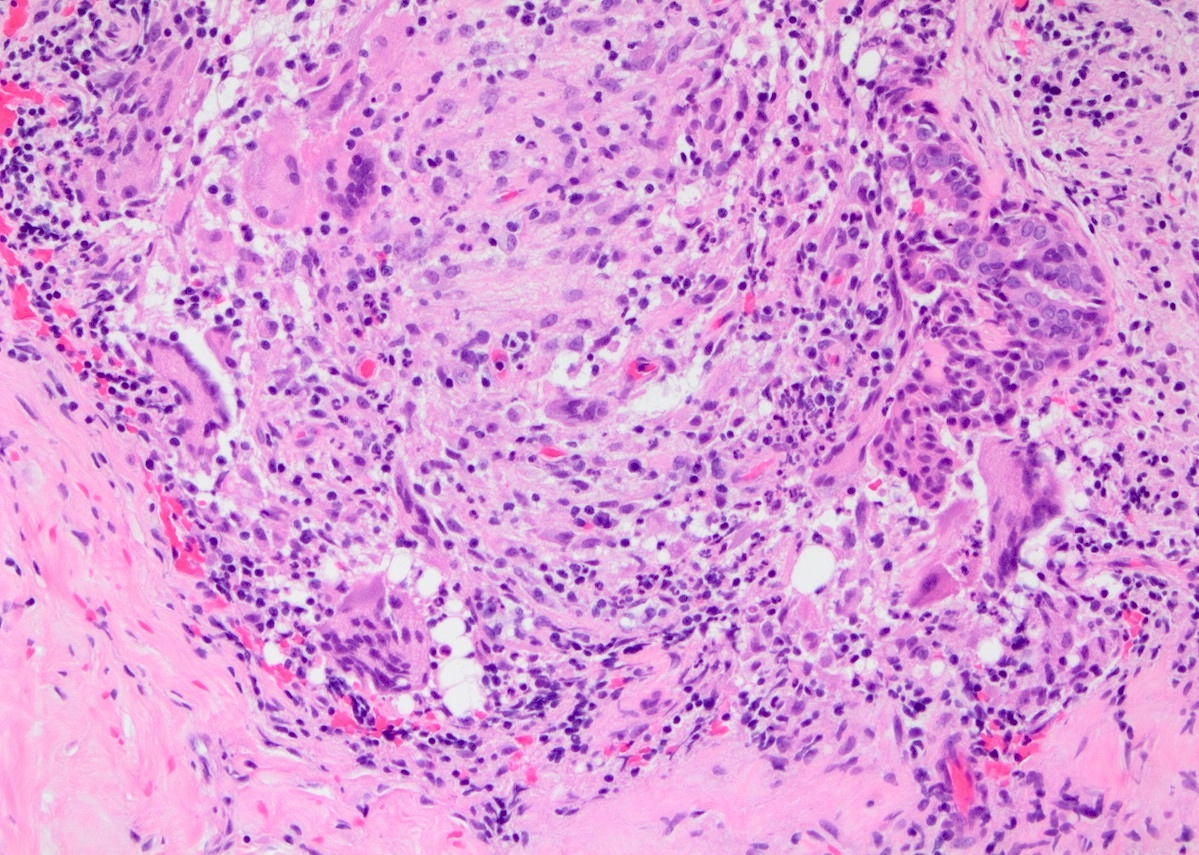

Microscopic (histologic) description

- Lobulocentric granulomatous inflammation (Pathology 2004;36:254)

- Granulomas often contain neutrophils

- Neutrophils can create microabscesses; overlapping features with cystic neutrophilic granulomatous mastitis

- Multinucleated giant cells, lymphocytes, plasma cells and eosinophils within and around lobules

- Extensive inflammation might obliterate lobulocentric distribution

- Caseous necrosis not present

- Schauman and asteroid bodies not common

Microscopic (histologic) images